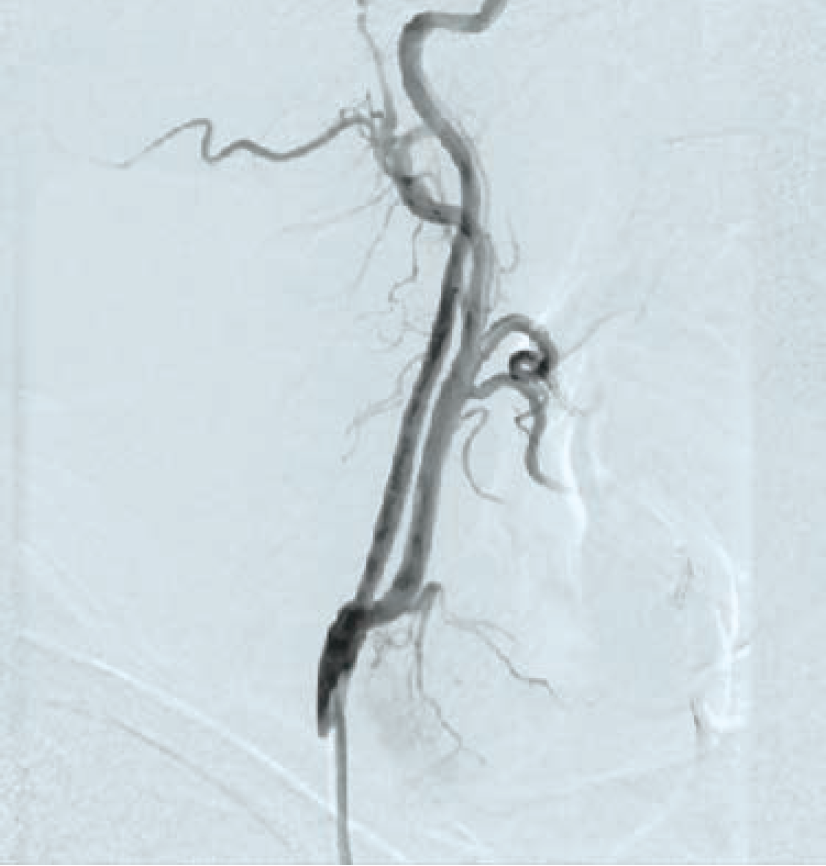

Following aseptic measures and under local anesthesia, a 7 French (Fr) right femoral access was obtained using a routine-length sheath. An .035-inch J-tip guide wire was then parked at the right common carotid artery (RCCA) using a 5 Fr Judkins right catheter, exchanged by a 7 Fr multipurpose guide. This was followed by advancement of a FilterWire EZ (Boston Scientific) across the ostial internal carotid artery stenosis, and deployed in the distal part of the extracranial ICA (Figure 2). After deployment of the FilterWire EZ, a direct stenting strategy was adopted to minimize thromboembolization. A 6 mm x 40 mm self-expanding stent was deployed at the RICA ostium (Figure 3). To our surprise, the view after stent placement showed zero flow into the distal RICA. (Figure 4) The reason appeared to be choking of the filter due to thromboembolization. The filter appeared to be overwhelmed by the volume of the debris captured. A 6 Fr Export catheter (Medtronic) was employed to suction debris from the distal ICA (Figure 5). We also administered pharmacotherapy using intra-arterial nitrate boluses and a weight-based tirofiban bolus. After these measures, there was fair flow into the distal ICA. During the period of no flow, the patient had transient hemispheric ischemic signs and an oropharyngeal airway was required, but his vitals remained stable. These symptoms rapidly resolved after establishment of ICA flow. After establishing blood flow, the proximal half of the stent that remained under-expanded was post dilated using a 4.5 mm noncompliant balloon at 12 atmospheres (Figure 6). Post dilatation, the angiographic view demonstrated good stent expansion and adequate distal flow (Figure 7). The distal protection device was then successfully removed using its retrieval sheath. The final DSA angiogram revealed excellent flow into the distal carotid (Figure 8A) and intracranial vasculature (Figure 8B), confirming no intracranial embolization. The guide was then safely removed over the .035-inch guide wire.